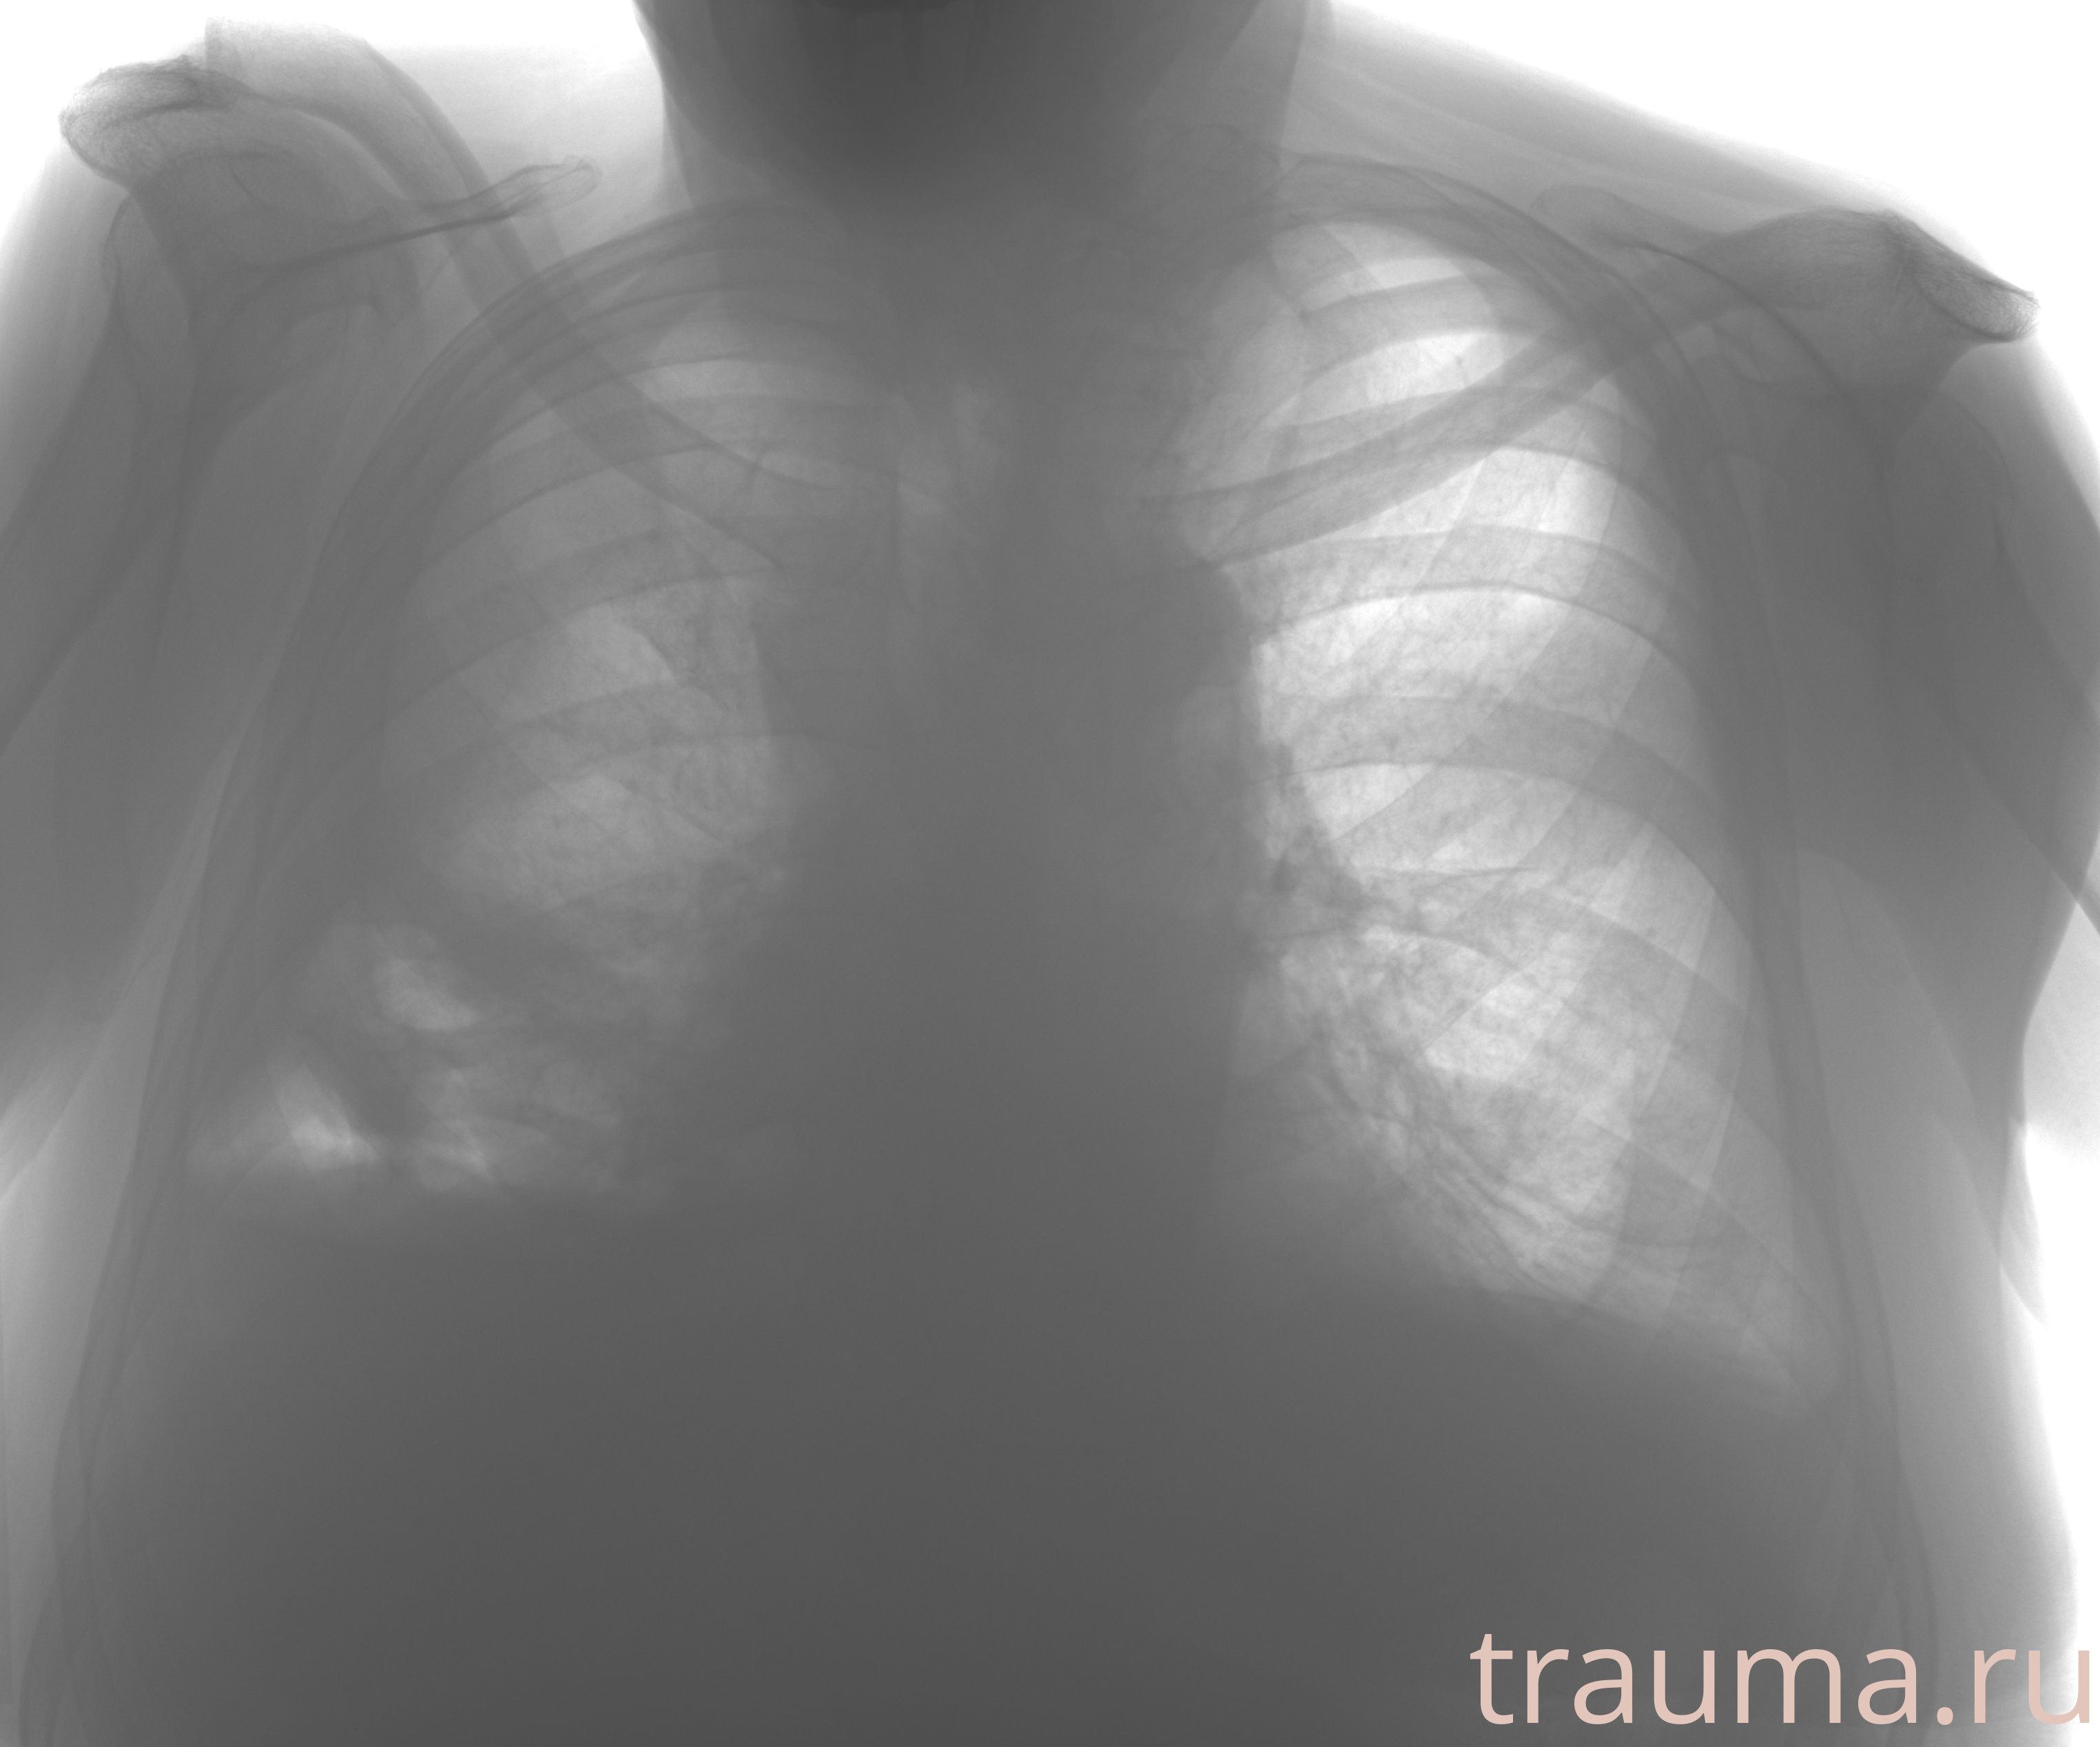

Рентген на дому: по вашему адресу приезжает врач-рентгенолог, травматолог-ортопед с мобильным рентгеновским аппаратом, проводит диагностику травмы или заболевания, делает необходимые рентгенограммы, дает рекомендации по дальнейшему лечению. Получить качественные снимки в домашних условиях возможно благодаря уникальной методике, разработанной МосРентген Центром для института  Склифосовского